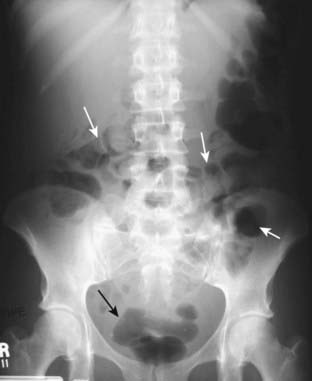

Figure 13-2 Normal prone abdomen.

In the prone position, the ascending and descending colon and the rectosigmoid—all posterior structures—are the highest parts of the large bowel and thus most likely to fill with air. There is air seen in the S-shaped rectosigmoid (solid black arrow) and throughout the remainder of the colon (solid white arrows).